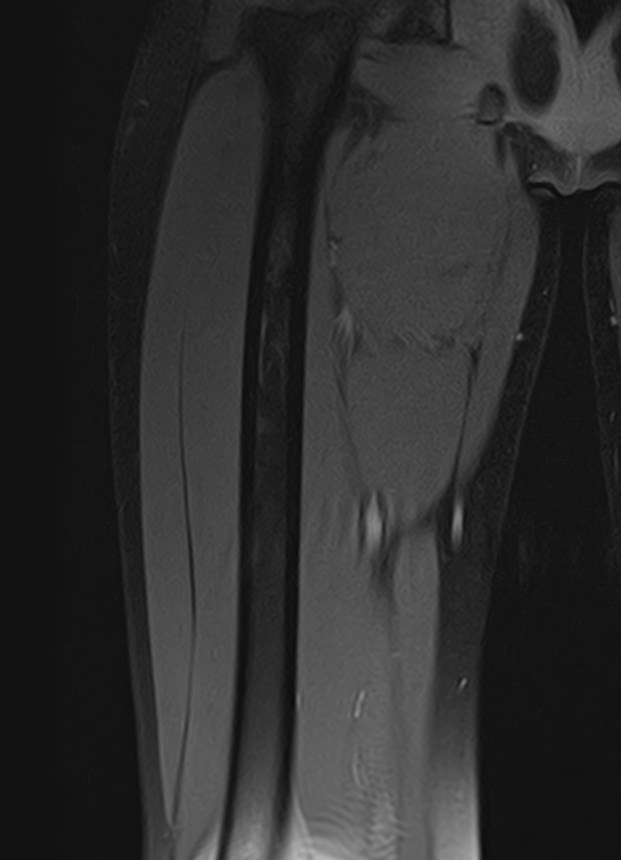

Магнитно-резонансная томография мягких тканей широко используется для детальной визуализации мягкотканных структур.

С помощью МРТ можно оценить состояние мышц, фасций, межфасциальных пространств, синовиальных оболочек, связок, сухожилий, сосудисто-нервных пучков, лимфоузлов и лимфатических протоков, надкостницы, кожи, подкожно-жировой клетчатки.

Метод магнитно-резонансной томографии по сравнению с другими исследованиями дает наиболее полную информацию о состоянии мягкотканных структур (по сравнению с УЗИ, традиционным рентгеновским исследованием и КТ). Кроме того, для повышения диагностической визуализации, например, при подозрении на развитие опухолевых процессов, дополнительно применяется контрастное усиление путем внутривенного введения гадолиниевого контрастного препарата.

В клинике «Доступная медицина» исследование выполняется на современном высокопольном томографе закрытого типа TOSHIBA VANTAGE TITAN 1,5 Тесла, который создает изображения с высокой детализацией мягкотканных структур за счет послойного сканирования в различных плоскостях.